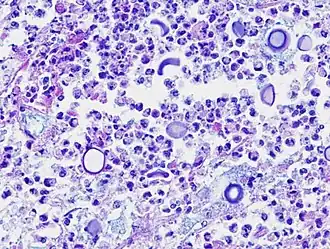

![]() Микрофотография возбудителя заболевания | |